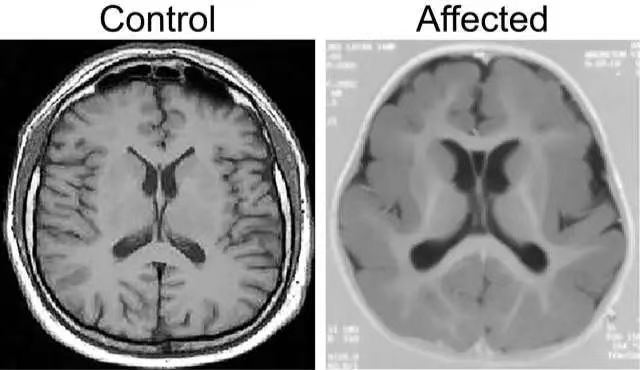

巨腦回畸形

巨腦回畸形(pachygyria)屬于神經(jīng)元移行異常性病變,神經(jīng)元移行障礙性疾病在腦部先天性疾病中所占比例大約為十萬分之一,既往的研究發(fā)現(xiàn),宮內感染、缺氧、中毒、外傷、接觸放射線等損害,可在胎兒神經(jīng)系統(tǒng)發(fā)育過程中影響成神經(jīng)細胞移行,造成神經(jīng)移行障礙。病因及常見疾病巨腦回畸形是一種神經(jīng)元移行異常性疾病,神經(jīng)元的移行是非常復雜的過程,這一過程一般從胚胎2個月~6個月,持續(xù)時間約3個月左右。而神經(jīng)元的異常是由于大腦皮質的發(fā)育發(fā)生了變異,從而發(fā)生一系列各種各樣的畸形,病理因素干擾的時間和程度不同,所出現(xiàn)的移行異常病變亦各異,神經(jīng)元移行障礙常以皮層發(fā)育為特征,越早發(fā)生畸形越嚴重,如腦裂畸形;越晚發(fā)生畸形較輕,如灰質異位和微腦回畸形。引起巨腦回病理干擾大多見于妊娠第11~16周,如果神經(jīng)元較晚發(fā)生移行,那么神經(jīng)元移行將受到阻礙,將不能形成正常腦表面皮層,導致了腦皮層增厚。此外較早發(fā)生移行的神經(jīng)元軸突和樹突在層狀壞死區(qū)中斷、退變,而使腦白質變薄。由于白質的發(fā)育不良常常導致腦室的擴張積水;因胼胝體發(fā)育期與神經(jīng)元的移行時間有重合,故常常伴有胼胝體的發(fā)育不良。正常的人類大腦皮層會皺折成一定數(shù)量的溝回和裂,根據(jù)這些溝回可把大腦皮層分成各個葉,而各葉的大腦皮層有著不同的機能區(qū)域,這些都是人類感覺、運動及情感中樞。而巨腦回畸形的大腦皮層腦回寬大扁平,腦溝淺小,皮層厚,灰-白質界面光滑不清,這就可能導致大腦上各種功能區(qū)域的缺陷。鑒別診斷臨床上患者常有不同程度的精神、運動及智能障礙,嚴重者表現(xiàn)為智力遲鈍,甚至生后不能存活,而存活者也常有智力低下,伴發(fā)癲癇,預后不良。巨腦回畸形的表現(xiàn)為腦回明顯寬大、腦溝淺小、皮層增厚為其主要特征,可兩側大腦對稱性出現(xiàn),也可局限一側單獨發(fā)生,程度重者腦溝腦回完全消失、腦表面光滑,累及全腦皮質層,也稱為光滑腦或無腦回畸形。檢查CT和MRI均是現(xiàn)如今診斷巨腦回畸形的主要檢查方法,但MRI具有多序列、多參數(shù)、多方位的成像功能,能提供優(yōu)良的組織分辨率和空間分辨率,在顯示巨腦回畸形的病理特征方面比CT有著更大優(yōu)勢。MRI通過不同加權像上信號的變化和多方位的成像,可以比CT更準確地顯示粗大的腦回、增厚的灰質。對于所合并的顱腦先天畸形,MRI能敏感地發(fā)現(xiàn)腦裂畸形的類型,可以更直觀全面地顯示胼胝體發(fā)育不良的程度和范圍,清楚顯示多個小腦回畸形的細小腦回和腦溝。治療原則現(xiàn)如今針對此類腦癱患兒無特殊治療,故關健是做好孕期保健及產(chǎn)前診斷工作,避免巨腦回畸形兒的出生。